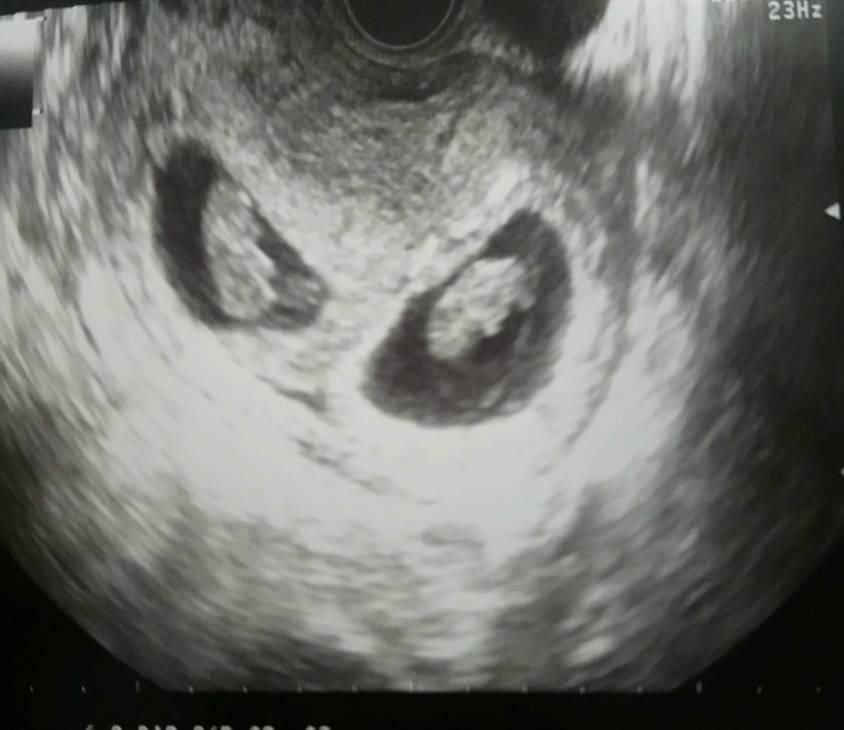

Ja dziś miałam wizytę u lekarza, dopiero od dziś mam kartę ciąży. Zlecono mi badania, wpisano recepty i mam się oszczędzać. Na szczęście udało się już dziś usłyszeć serduszka [emoji3590][emoji3590]

Termin z OM 5.10, ale wiem że będzie wcześniej, w końcu to bliźniaki [emoji6]

Termin z OM 5.10, ale wiem że będzie wcześniej, w końcu to bliźniaki [emoji6]Zobacz załącznik 1085293